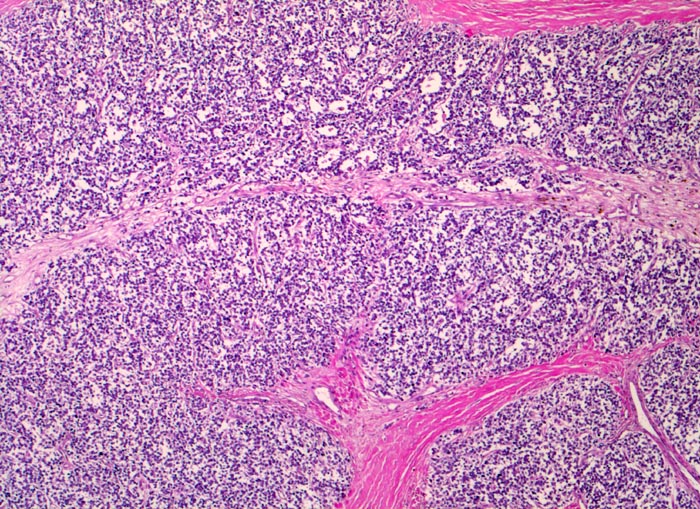

Ewing-Sarkom

Monotoner Rasen kleiner runder blauer Tumorzellen durchzogen von bindegewebigen Septen.

Zunehmende Schmerzen im rechten Oberschenkel mit Weichteilschwellung- und Erwärmung seit mehreren Monaten. Keine Traumaanamnese. Klinisch wird zunächst eine Osteomyelitis vermutet.

Histologie

50